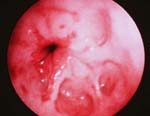

Αμερικανοί ερευνητές ανέπτυξαν ένα απλό διαγνωστικό τεστ για την πρώιμη διάγνωση του οισοφάγου Barrett, που δημιουργεί υποσχέσεις πρόληψης των θανάτων από οισοφαγικό αδενοκαρκίνωμα, σύμφωνα με άρθρο του επιστημονικού εντύπου Science Translational Medicine.